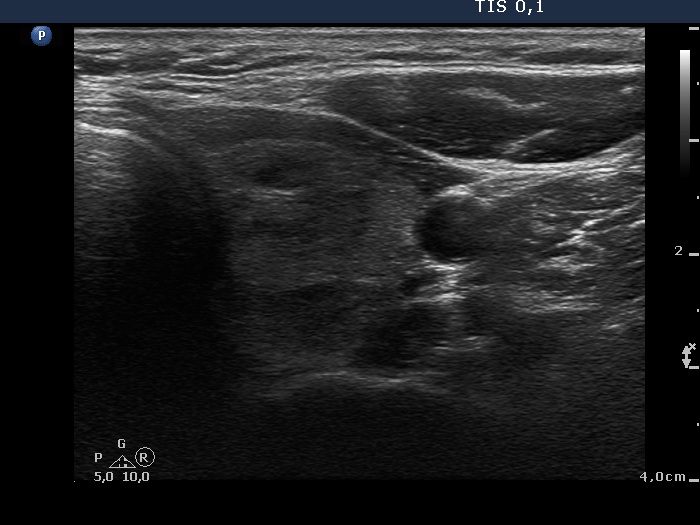

Ultrasonography: The thyroid was echonormal and contained multiple inhomogeneous, hyperechogenic nodules. There was a hypoechogenic lesion in the dorsal part or dorsal to the lower pole of the right lobe.

Aspiration cytology resulted in benign lesion which might correspond to parathyroid adenoma.